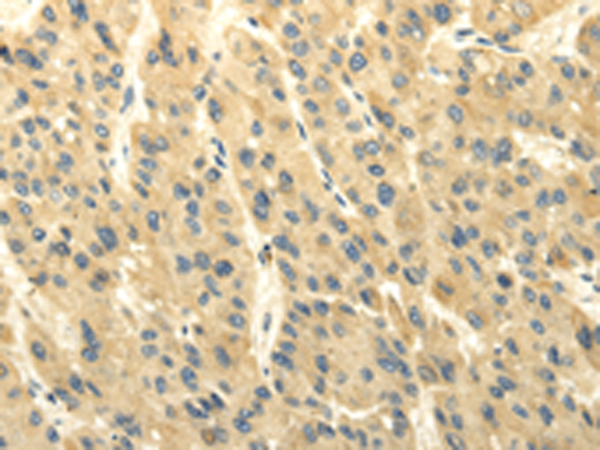

分类: 科研抗体货号: P08827别名: CARB应用: WB,IHC反应种属: Human, Mouse, Rat